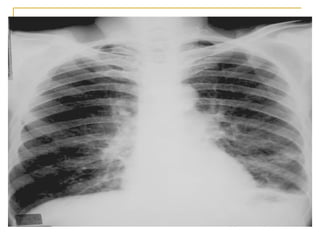

Patrón intersticial   Se caracteriza por la existencia de líneas o rayas en el parenquima pulmonar   Patrón lineal o linfangítico, que corresponden al engrosamiento de los septos interlobulillares infiltrado  intersticial  inflamatorio y depósito anómalo de fibras del tejido conectivo que pueden conducir a una fibrosis pulmonar que a su vez puede evolucionar hacia un patrón en pana l

Opacidades intersticiales de patrón reticular grueso, de predominio periférico, con áreas que sugieren patrón de "panal de abejas". Neumonía  intersticial  descamativa :  zonas de pulmón sano de inflamación,  macrófagos   de fibrosis intersticial  fibroblastos proliferantes  cambios de pulmón en panal.  heterogeneidad

Opacidades en "vidrio esmerilado". Y   distorsión de la arquitectura pulmonar por fibrosis.  Y panal de avejas